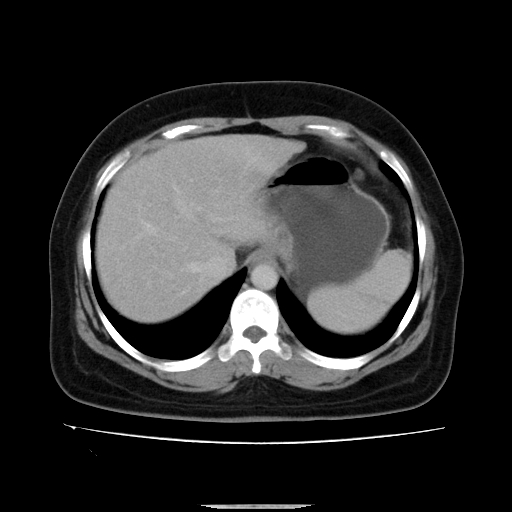

标题: CT14225:女性46岁。当地B超示肝内占位,来我院作CT检查。请 [打印本页]

标题: CT14225:女性46岁。当地B超示肝内占位,来我院作CT检查。请

右叶肝癌灶;慢性胆囊炎,不除外占位;;副脾可能性

肝内结节强化特点符合原发性肝癌表现,脾脏改变考虑为增大及先天发育所致。

动脉期病原灶明显强化高于肝密度且中央有无强化区,静脉期强化程度下降明显,延迟低于肝密度,考虑肝腺瘤可能性大,

符合肝癌表现,脾脏大(肝硬化?)

肝内结节强化特点:快进快出符合原发性肝癌表现

此患者虽然符合快进的特点,却不符合快出的特点,因为门脉期几乎是等密度,不符合肝癌的增强表现,所以我考虑肝局灶性结节增生可能性大

肝内结节强化特点符合原发性肝癌表现。脾大。